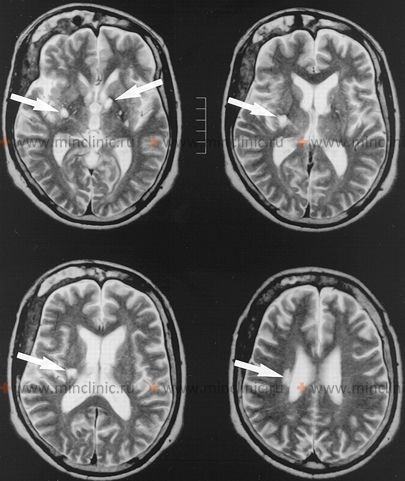

თავის ტვინის კომპიუტერული ტომოგრაფიის (კტ) სკანირებას აქვს შეზღუდული მგრძნობელობა ლაკუნური ინფარქტების გამოსავლენად, განსაკუთრებით მწვავე ფაზაში ან როდესაც ისინი ძალიან მცირეა [1, 5]. ქრონიკული ლაკუნები შეიძლება გამოჩნდეს როგორც მცირე, კარგად განსაზღვრული ჰიპოატენუაციური (მუქი) დაზიანებები [5]. მაგნიტურ-რეზონანსული ტომოგრაფია (მრტ) მნიშვნელოვნად უფრო მგრძნობიარეა ვიდრე კტ როგორც მწვავე, ასევე ქრონიკული ლაკუნური ინფარქტების იდენტიფიცირებისთვის სუპრატენტორიულ და ინფრატენტორიულ ლოკაციებზე [1, 5]. სპეციფიკური მიმდევრობები, როგორიცაა დიფუზიურ-აწონილი ვიზუალიზაცია (DWI), გადამწყვეტია მწვავე ლაკუნების გამოსავლენად, ხოლო FLAIR და T2-აწონილი გამოსახულებები შესანიშნავია ქრონიკული ლაკუნების ვიზუალიზაციისთვის და მცირე სისხლძარღვების დაავადების საერთო ტვირთის შესაფასებლად [5].

მრტ ნათლად აჩვენებს ლაკუნური ინფარქტების დამახასიათებელ მდებარეობებს ღრმა რუხი ნივთიერების სტრუქტურებში (მაგ., ბაზალური განგლიები, თალამუსი), შიგნითა კაფსულაში, სხივოსან გვირგვინსა და ტვინის ღეროში (ხიდი), ისე რომ არ აზიანებს ცერებრალურ ქერქს [1, 5]. კრიტიკულად მნიშვნელოვანია, რომ მრტ-ს ასევე შეუძლია აღმოაჩინოს მცირე ინფარქტები, რომლებიც მოიცავს ცერებრალურ ქერქს ან ზედაპირულად მდებარეობს სუბკორტიკალურ თეთრ ნივთიერებაში უშუალოდ ქერქის მიმდებარედ [1]. ასეთი ინფარქტები, თუნდაც მცირე, ტიპიურად გამოწვეულია ემბოლიით (გულიდან, აორტიდან ან დიდი არტერიებიდან) და არა ერთი მცირე გამჭოლი არტერიის შინაგანი ოკლუზიით (ლიპოჰიალინოზის ან მიკროათერომის გამო), რაც განსაზღვრავს ლაკუნურ ინფარქტს [1, 2]. ამრიგად, ვიზუალიზაციაზე კორტიკალური ჩართულობის არსებობა ფაქტობრივად გამორიცხავს ლაკუნური ინფარქტის დიაგნოზს და მიუთითებს ემბოლიურ ეტიოლოგიაზე [1].